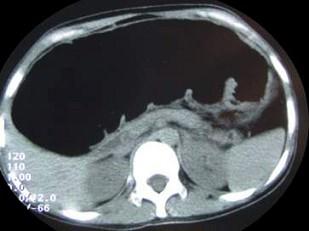

问题 女,30岁,便秘、腹痛腹胀多年,CT检查如图,最可能的诊断是 ( )

选项 A、结肠肠扭转 B、结肠肠栓塞 C、先天性巨结肠 D、结肠肠套叠 E、结肠肠梗阻

答案 C